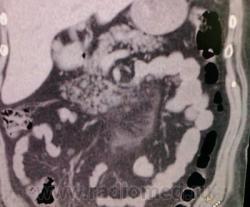

Прошу помочь КТ-специалистов. Медсестра 68 лет, частые боли в позвоночнике, непостоянные боли в животе. Направлена неврологом для исключения грыжи МПД поясничного отдела. Выявлены дегенеративные вараженные изменения позвоночника. По УЗИ норма, Hb=116 (начало 2009).На КТ: в брыжейке тощей кишки уплотнение жировой клетчатки (-45...-60ед.Н) размерами 12х5х7 см, окружает верхнебрыжеечную артерию, пронизано сосудами. Лимфоузлы брыжейки 0.5-1-1.5 см. Парааортальные л/у единичные, не увеличены.Контрастирования не проводилось - амбулаторное обращение. В понедельник давать заключение. Подозреваю ангиолипому. Буду рекомендовать обследование в стационаре.

Реконструкции

В вашем случае виден очень характерный для панникулита симптом ободка нормальной жировой плотности вокруг сосудов (симптом halo), ход сосудов не изменен, смещения или сдавления нет.